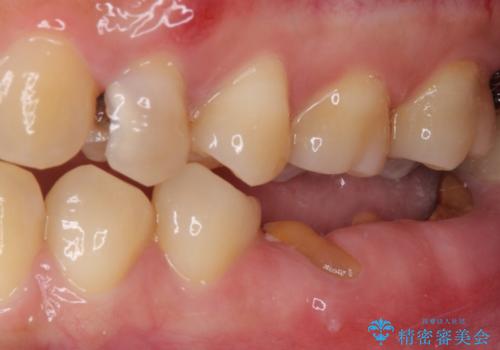

- 奥歯に問題が多くて困っているとのことで来院された患者様です。

開咬により奥歯のみが接触している状態で、前歯部にほとんど接触のない状態で、奥歯に非常に負担のかかる咬み合わせでした。

また、欠損や根管治療の必要な歯など、むし歯による問題も多く散見されました。

まずはむし歯の治療を行い、その後ワイヤー矯正にて咬み合わせを改善し、途中インプラント埋入を行い、矯正治療後に補綴治療を行うこととしました。